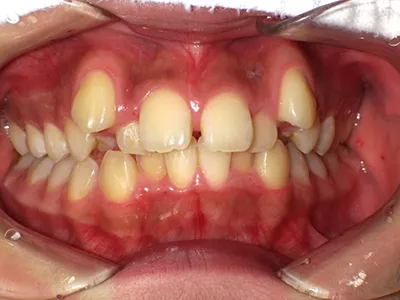

症例4

before

after

| 主訴 | 八重歯が気になる、歯並びきれいにしたい |

|---|---|

| 治療内容 | ワイヤー矯正 |

| 治療期間 | 1年 |

| 費用 | 770,000円(税込) |

| リスク・副作用 | 歯牙移動による痛み、染みる症状が出てしまうことがあります |